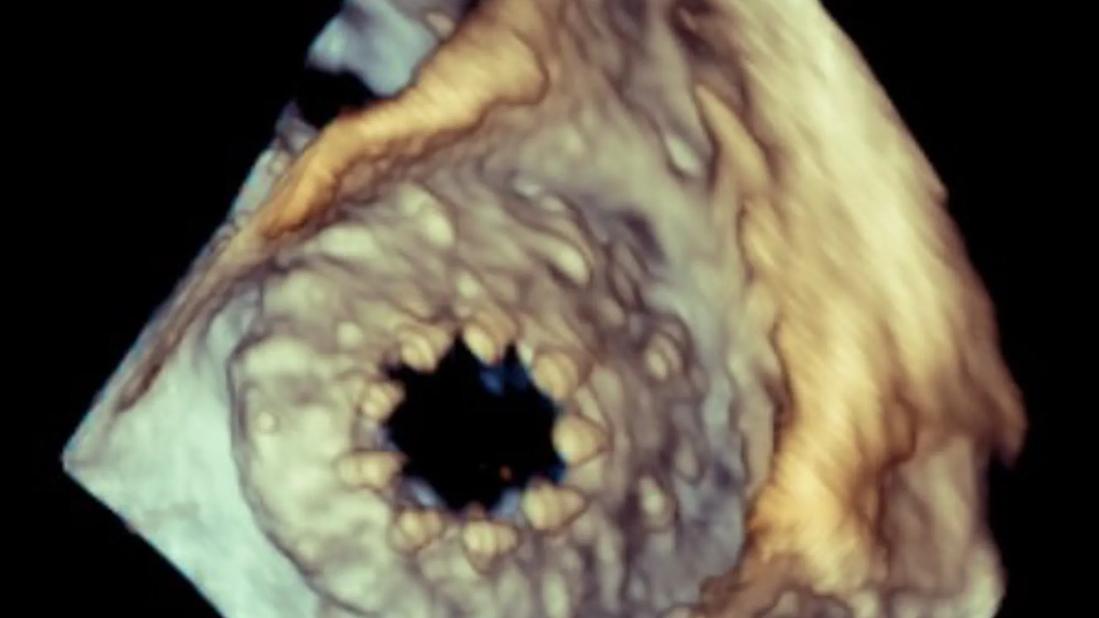

Tricuspid valve with severe regurgitation

3D transesophageal echocardiography (TEE) image of a tricuspid valve with severe regurgitation.